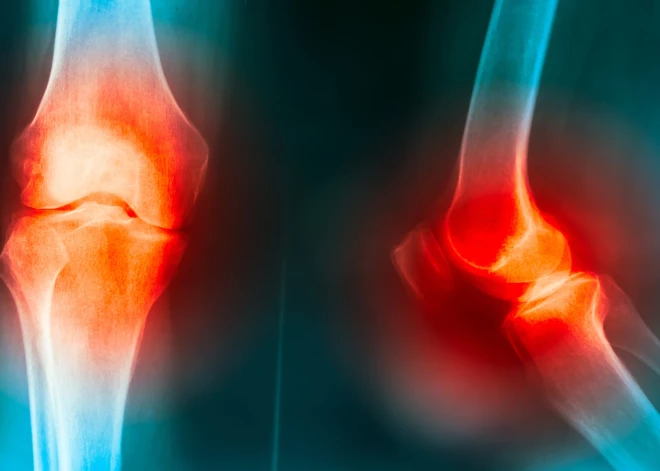

Ar vecumu mūsu ķermenis dabiski piedzīvo izmaiņas, kas skar arī mūsu balsta-kustību sistēmu. Šī sistēma sastāv no skeleta un muskuļiem, kas atbild par mūsu kustību un atbalstu. Locītavas savieno kaulus un nodrošina elastību, ļaujot mums pārvietoties. Tomēr novecošanās procesā locītavas zaudē savas sākotnējās īpašības – tās kļūst stīvākas, samazinās skrimšļa daudzums un palielinās berze starp kauliem, kas izraisa sāpes un diskomfortu.

Vecumam pieaugot, locītavas sāk zaudēt savu elastību un kustīgumu. Tas notiek, jo skrimšļi, kas kalpo kā amortizatori starp kauliem, nolietojas un samazinās to biezums. Tā rezultātā locītavas kļūst stīvākas un var sākt sāpēt, it īpaši pēc fiziskām aktivitātēm. Arī šķidruma daudzums locītavās samazinās, kas veicina berzi un diskomfortu. Šīs izmaiņas, ja tās netiek kontrolētas, var novest pie nopietnām locītavu slimībām, piemēram, osteoartrīta.

Osteoartrīts ir viena no visizplatītākajām locītavu slimībām, kas galvenokārt skar gados vecākus cilvēkus. Tā ir hroniska slimība, kas sākumā skar skrimšļa kārtu, pakāpeniski bojājot un nolietojot to. Tas izraisa locītavu sāpes, stīvumu un ierobežotu kustīgumu. Ar laiku osteoartrīts var ietekmēt arī muskuļus, kaulus un saites, padarot locītavas vēl mazāk kustīgas.

Šīs slimības izplatība ir ļoti augsta – pēc 65 gadiem trīs no četriem cilvēkiem cieš no osteoartrīta. Tas bieži notiek nemanāmi, tāpēc ir svarīgi pievērst uzmanību pirmajām pazīmēm un uzsākt profilaksi jau jaunākā vecumā.